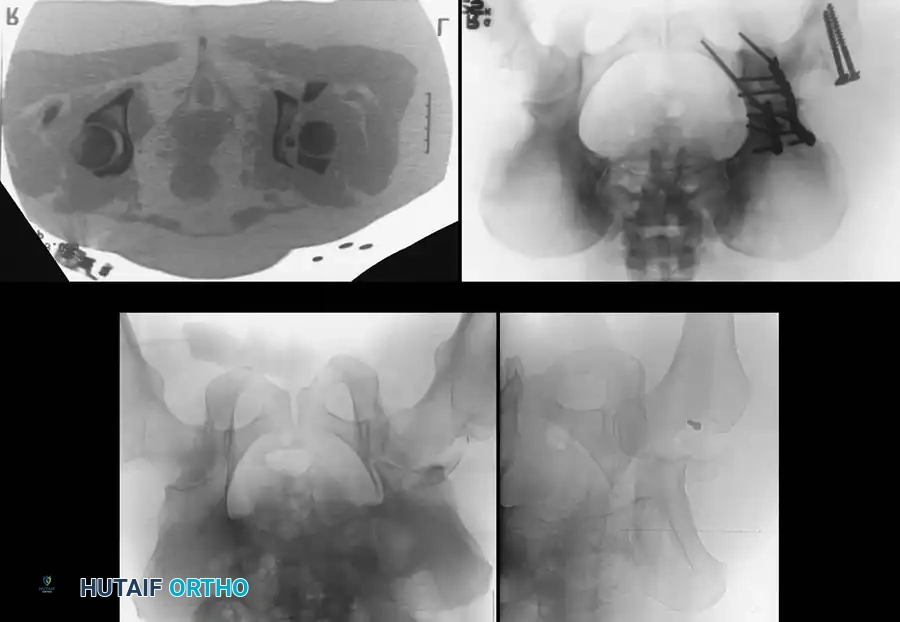

Associated Surgical & Radiographic Imaging

Hutaifortho's Orthopaedic Diagram